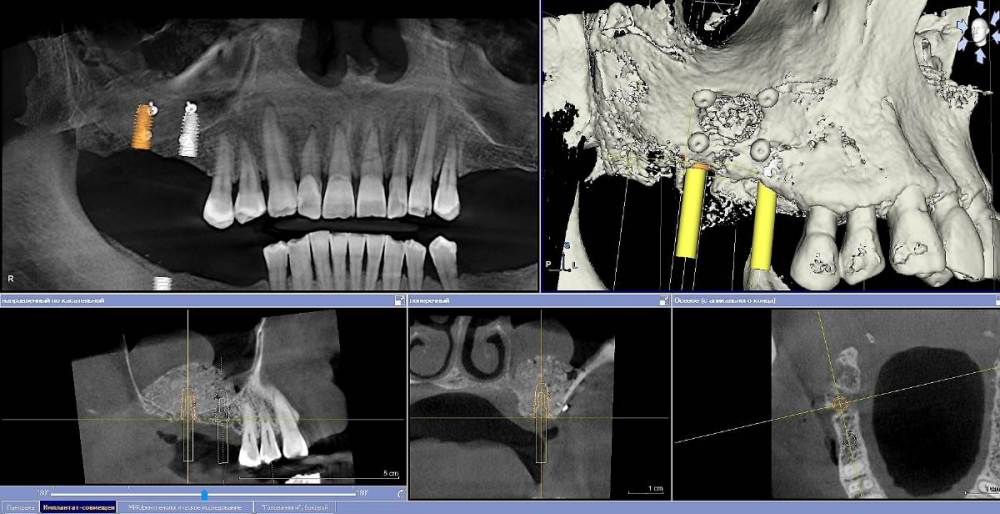

Ponchik Опубликовано 8 октября, 2021 Поделиться Опубликовано 8 октября, 2021 Как лучше поступить? Сделать два окна и через одно убрать кисту, а через второе сделать синуслифтинг, или синуслифтинг вторым этапом? Киста ли это? Ссылка на комментарий

pit Опубликовано 9 октября, 2021 Поделиться Опубликовано 9 октября, 2021 08.10.2021 в 11:01, Ponchik сказал: Как лучше поступить? Сделать два окна и через одно убрать кисту, а через второе сделать синуслифтинг, или синуслифтинг вторым этапом? Киста ли это? Составить полноценный план протезирования. Если Вы реализуете Ваш план вся нагрузка придется на импланты 16 17 зубов. Антагонисты дистопированы, премоляров нет, с другой стороны концевой дефект. Зачем такая работа? Но если это первый этап в рациональном протезировании, то пункция с эвакуацией содержимого и ОСЛ+2 винта Ссылка на комментарий

Ponchik Опубликовано 10 октября, 2021 Автор Поделиться Опубликовано 10 октября, 2021 16 часов назад, pit сказал: Составить полноценный план протезирования. План такой - 46,47 удаление. ОСЛ с двух сторон. Два импланта (на нижней челюсти справа 3) на каждую сторону и протезирование. В реальности - создал окно, в том месте где ожидал кисту пунктировал, но попадал в просвет пазухи (когда промывал физраствором, он тёк в глотку) в итоге место двух пробных пункций (и даже разреза на 2-3мм) закрыл мембраной и добавил графта. На кт потом увидел куда убежала киста. Теперь будем посмотреть. Ссылка на комментарий